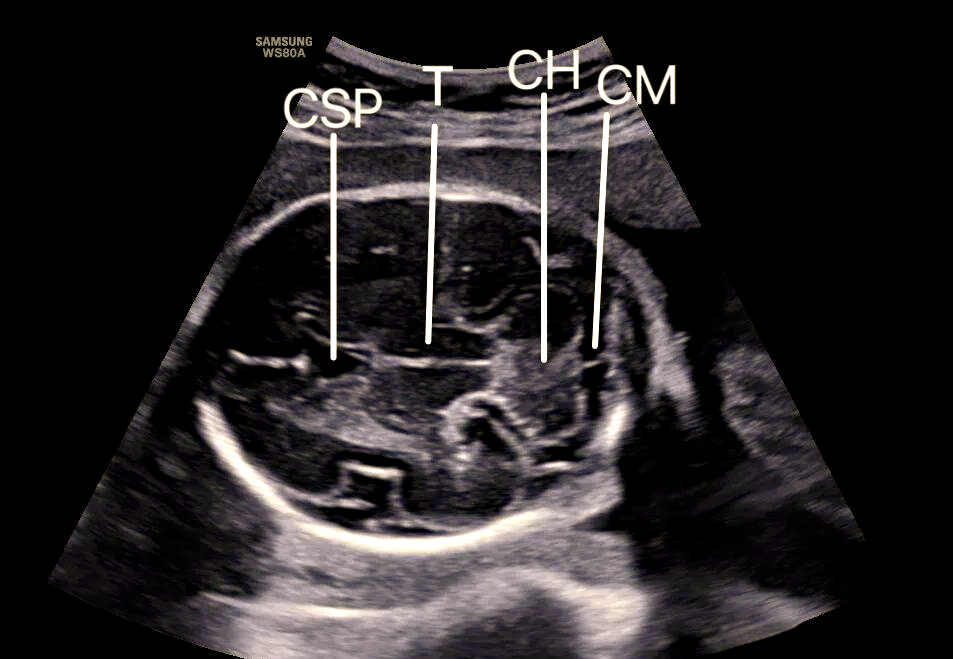

透明隔间腔图片

透明隔间腔,中间帆腔,vergae腔

透明隔间腔/vergae腔/中间帆腔

透明隔间腔 透明隔间腔是大脑内一个潜在的腔隙,位于两侧侧脑室之间

透明隔间腔是两侧侧脑室之间的间隔结构

胎儿透明隔腔的超声学习与了解